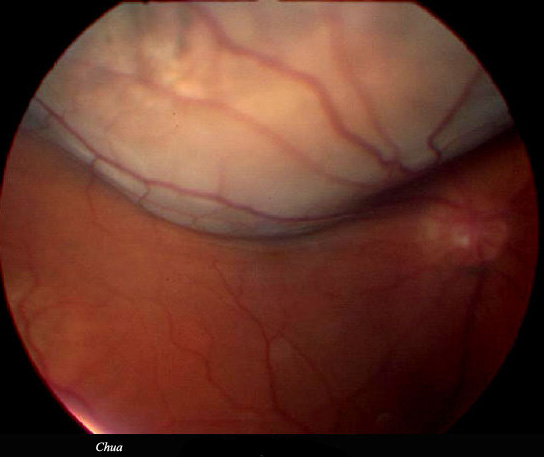

History: A patient presented with shadow over his inferior visual field. Fundal examination revealed a solid retinal detachment. Ultrasound suggests a choroidal lesion possibly melanoma. Patient was referred to the National Centre for further management.